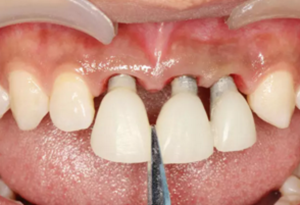

圖23 最終修復(fù)后即刻口內(nèi)像

(4)最終修復(fù)。種植體周圍軟組織改建成熟以后,進(jìn)行最終修復(fù)。本 病例采用兩步法印模技術(shù)精確記錄種植體的三維位置和種植體周圍軟組織穿 齦輪廓外形。 首先,口內(nèi)制取臨時冠及周圍軟硬組織的硅橡膠陰模,復(fù)制軟硬組織 表面形態(tài)。然后,取下臨時修復(fù)體,常規(guī)制取閉窗式種植體水平聚醚印模, 精確記錄種植體的三維位置,灌制含人工牙齦的超硬石膏模型。最后,去除 模型上的人工牙齦,將臨時修復(fù)體戴入到模型上,在臨時修復(fù)體周圍和硅橡 膠陰模內(nèi)注入人工牙齦,將陰模就位到含臨時冠的石膏模型上,精確轉(zhuǎn)移穿齦輪廓外形,獲得工作模型。 制作螺絲固位的一體化氧化鋯基臺冠,以切削方式制作完成后,表面 添加飾瓷來獲得理想的美觀效果。 術(shù)后7個月,戴入最終修復(fù)體,紅白美學(xué)效果滿意。

(5)復(fù)查。種植體周圍骨水平穩(wěn)定,齦乳頭及齦高點(diǎn)位置穩(wěn)定,齦緣 曲線形態(tài)理想,唇側(cè)軟硬輪廓良好,功能滿意,修復(fù)效果符合預(yù)期。